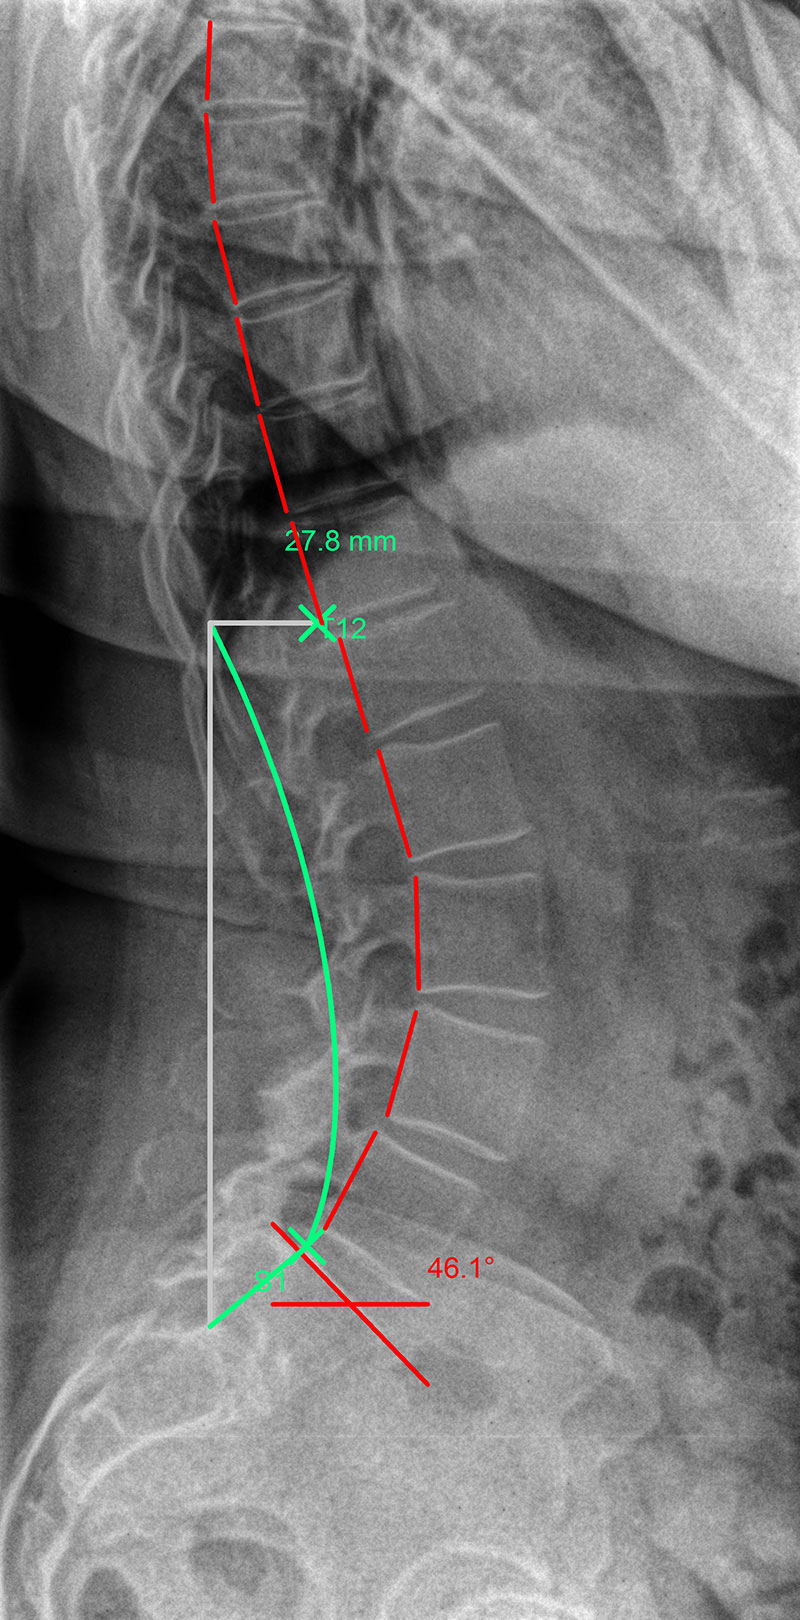

Hyperlordosis: |

The green line represents the ideal spinal curvature and the red line that of the patient’s spine in profile view.